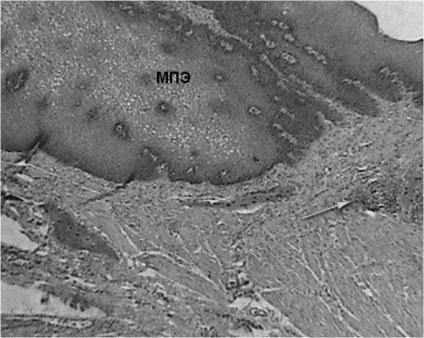

A szövettani vizsgálat a nyelőcső eltávolítása után végzett 3 esetben, a széleit a nyelőcső-mediasztinális sipoly után fibroezofagoskopii - 1 fő esetében. nyelőcső változások a stent minden esetben azonos, és képviseli a gyulladás különböző súlyosságú. A nyálkahártya talált szabálytalan hangsúlyos acanthosis, bazális réteg hiperaktivitás, dyskeratosis fejlesztésével a granulációs szövet a proximális és disztális végei a stent. A nyálkahártya alatti réteg feltárt infiltrációja limfociták, plazma sejtek és a makrofágok (ábra. 7).